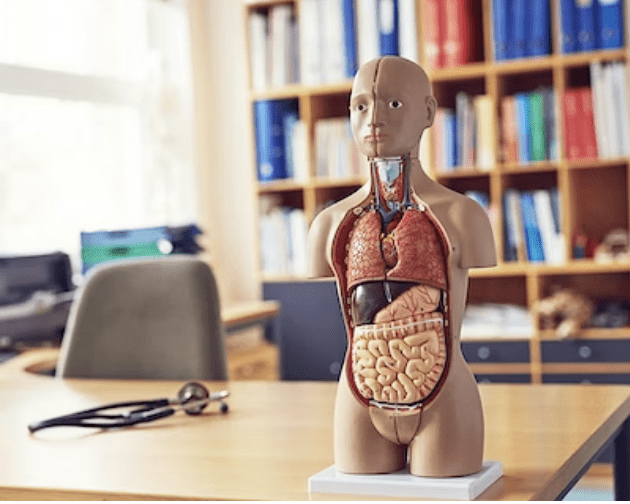

Med denne model får du det komplette overblik over hovedet og halsens anatomi. Modellen illustrere både den overfladiske og dybereliggende muskulatur, og viser desuden kar og nerver i relation til disse.

Modellen kan adskilles i 5 dele, idet kranietoppen kan aftages, og hjernen kan udtages og adskilles i 3 dele.

Modellen har målene 36 x 18 x 18 cm (højde x længde x bredde), vejer 2 kg og leveres på en hvid stander, som ligeledes er aftagelig.